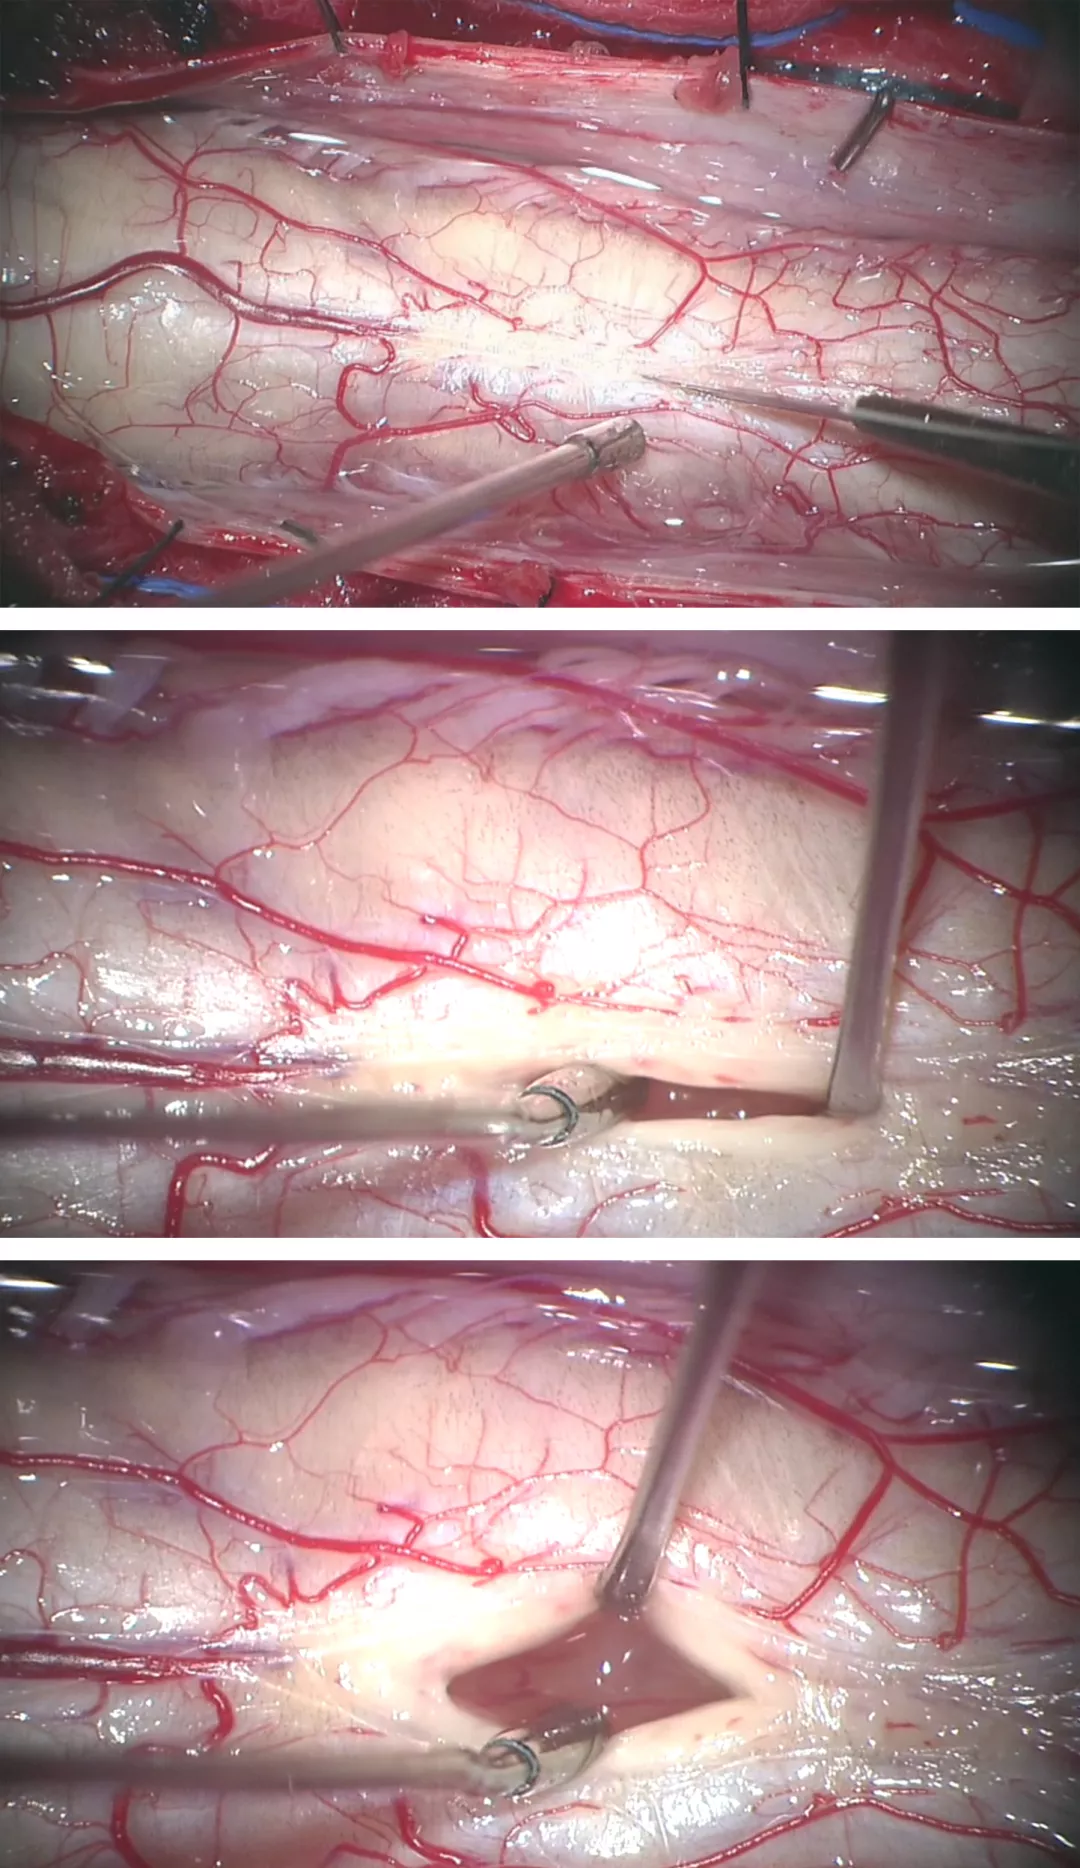

图7:采用娴熟的显微操作技术将瘤壁自菲薄的脊髓上剥离下来。由于肿瘤出血或空洞导致脊髓与肿瘤之间形成一个明显界面。大多数室管膜瘤和脊髓之间存在明显的肿瘤-脊髓界面。一般室管膜瘤的前方均有自脊髓前动脉发出的小动脉供血。在切除肿瘤时,这些肿瘤穿支血管要仔细分离、予以电凝后切断。盲目地牵拉会导致这些血管的撕裂,从而在止血过程中可能导致临近血管和脊髓的损伤。

图8:血管母细胞瘤是高度富含血供的肿瘤,同时由于其组织来源为软膜血管周围间叶组织而非间质组织,因而其分离应该限于软膜而尽量避免脊髓组织损伤。鉴于其血供丰富且边界清楚,血管母细胞瘤的切除最好采用整块切除。血管母细胞瘤通常位于后外侧沟(背根入口区)。这一类似血管畸形的瘤体在分离时应仔细对瘤体进行去血供。在切除过程中,可采用小功率双极进行电凝以缩小瘤体体积从而使其界面更加清楚,易于分离。血管母细胞瘤的囊性部分或空洞可使分离更加容易。在瘤体深部与脊髓之间由于反复的小出血或压迫会造成肿瘤瘤体与脊髓也有一层界面。

切除髓内血管母细胞瘤主要包含以下几个要点:1)蛛网膜和神经根的分离、小功率双极电凝瘤体表面以及瘤体与脊髓界面的识别与分离;2)软脊膜及脊髓的切开及肿瘤的暴露,尤其是体积巨大的肿瘤;3)在处理体积较大的血管母细胞瘤时,采用6-0 prolene缝线适当牵拉软脊膜以暴露瘤体,电凝供血动脉,最后完成瘤体分离后再切断引流静脉,最终切除肿瘤。